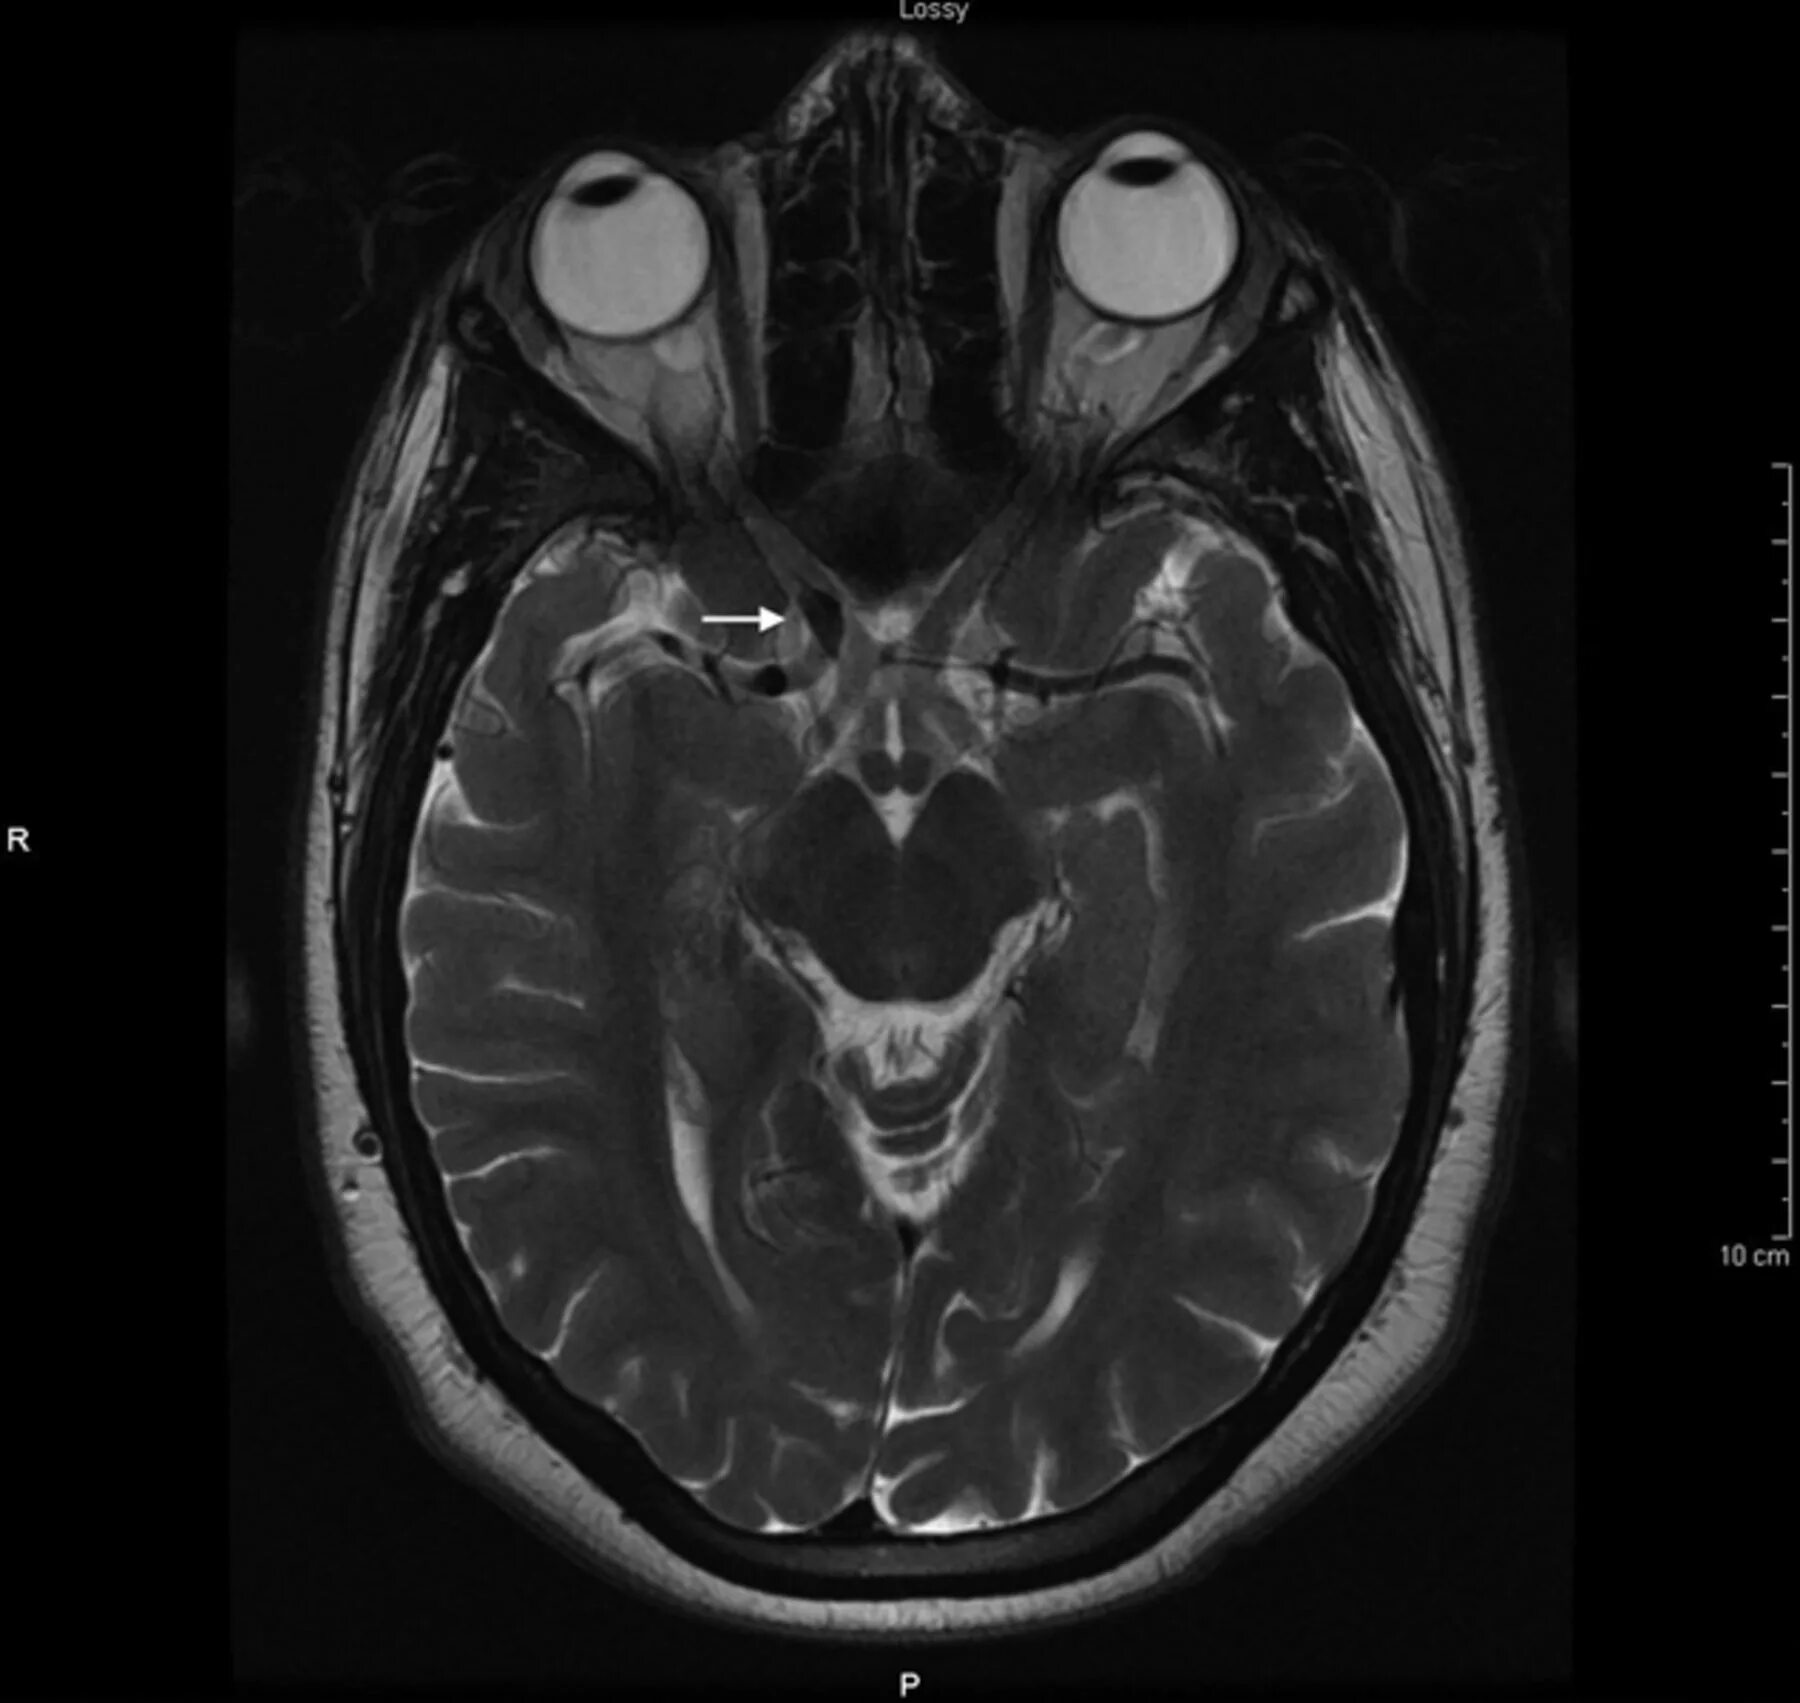

Нейроваскулярный конфликт нерва